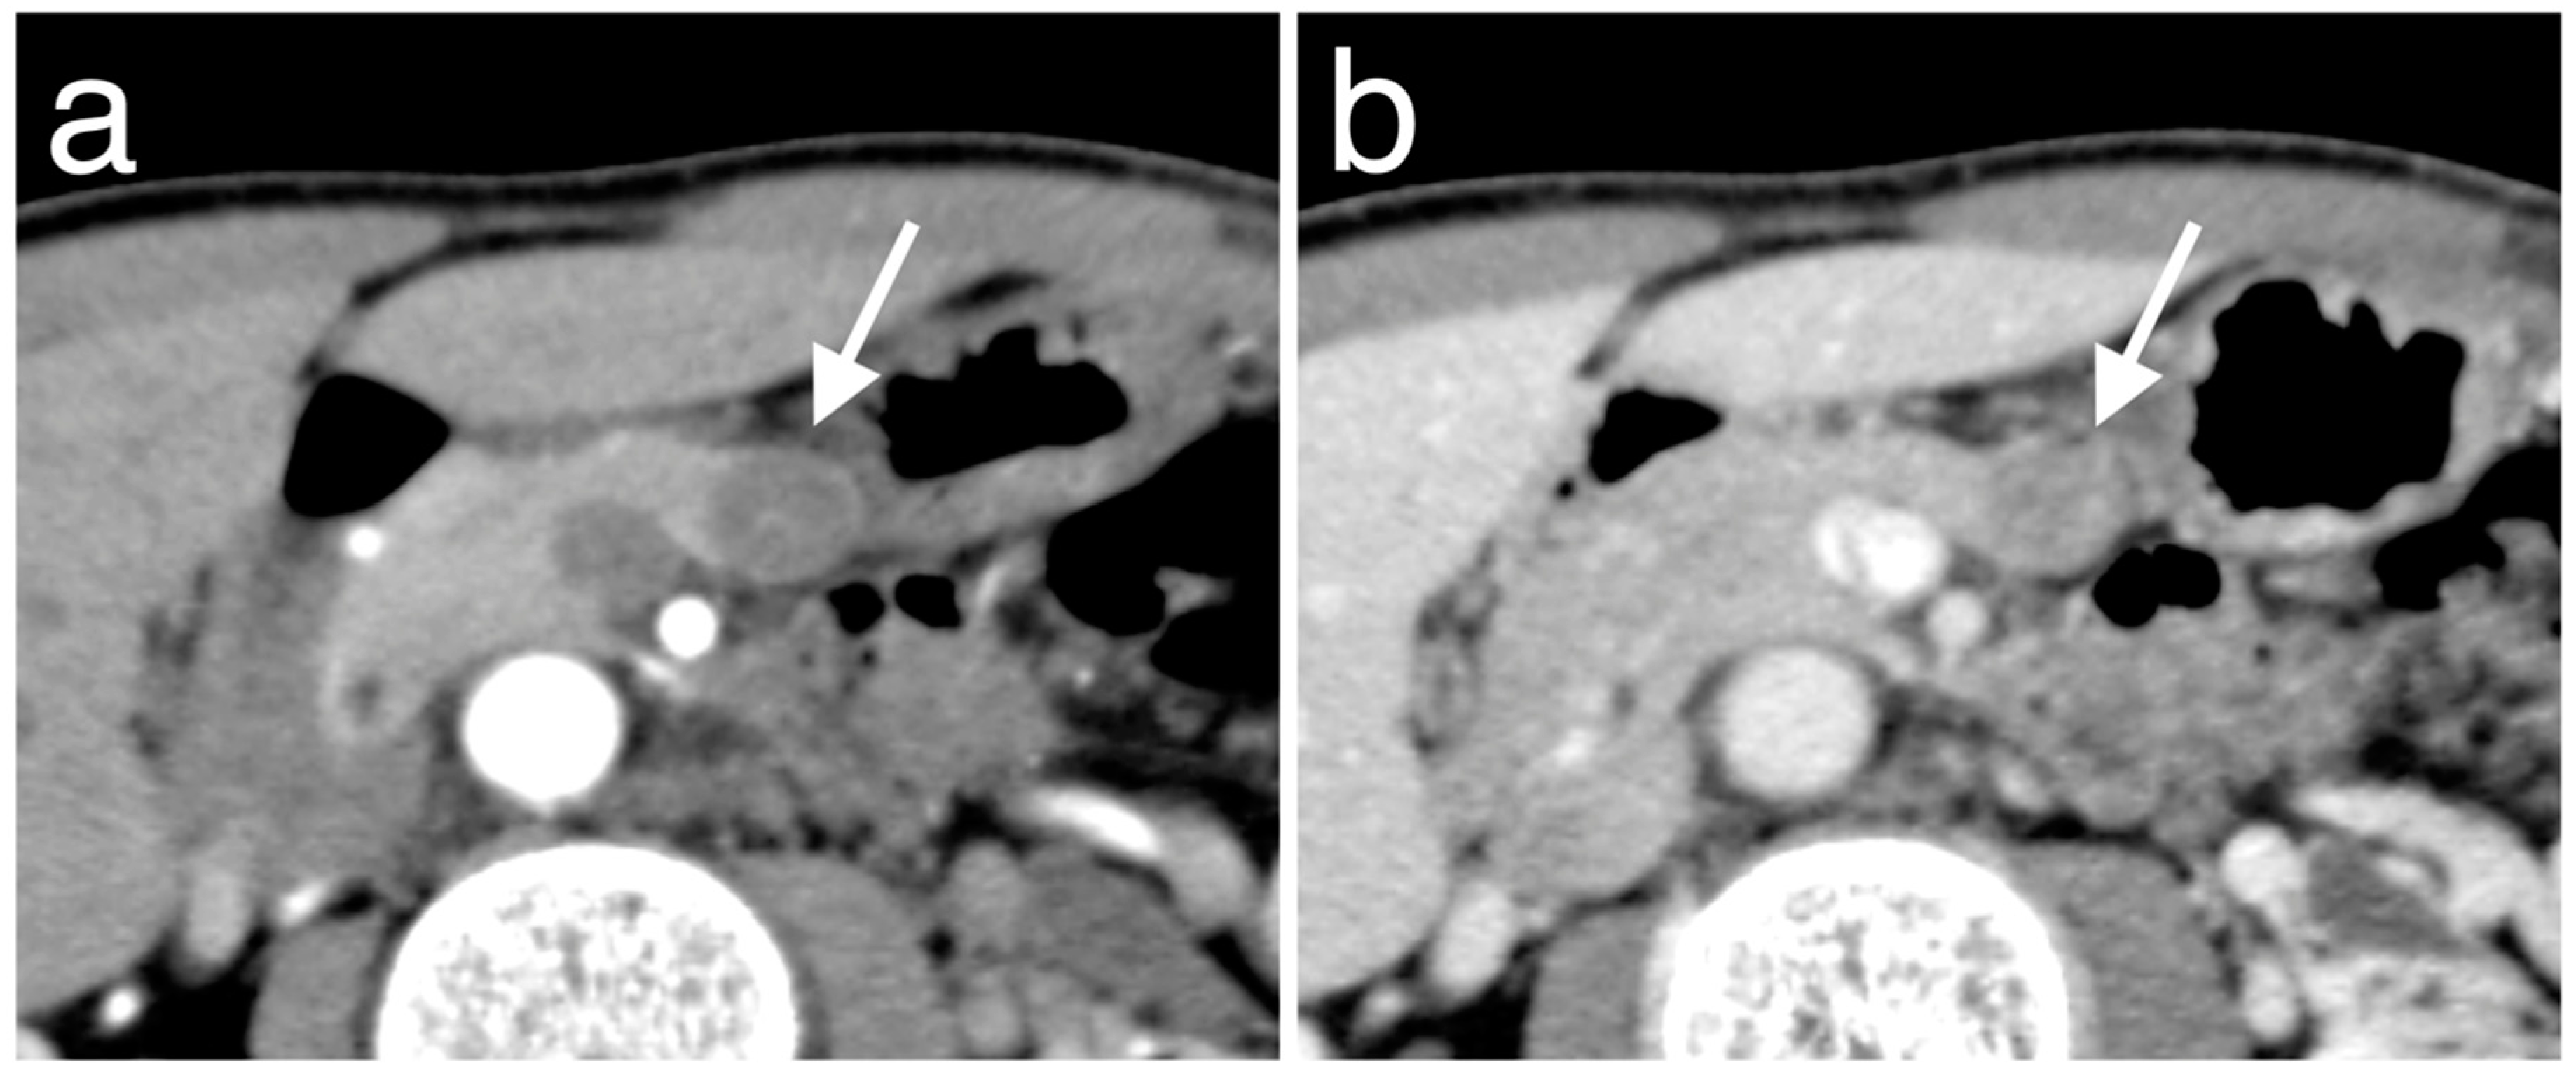

3.2. Morphological Features of Pan-NENs Associated with Low or High PAX6 Expression

| Cystic change | 1 | 5 | 0.46 | 1.00 |

| Calcification | 4 | 4 | 0.92 | 0.055 |

| Visible intratumoral vessel | 1 | 5 | 0.73 | 1.00 |

| Invasion into adjacent vascular | 2 | 3 | 0.63 | 0.29 |

| Main pancreatic duct dilatation | 1 | 2 | 0.84 | 0.52 |

| Upstream pancreatic atrophy | 2 | 1 | 0.64 | 0.11 |